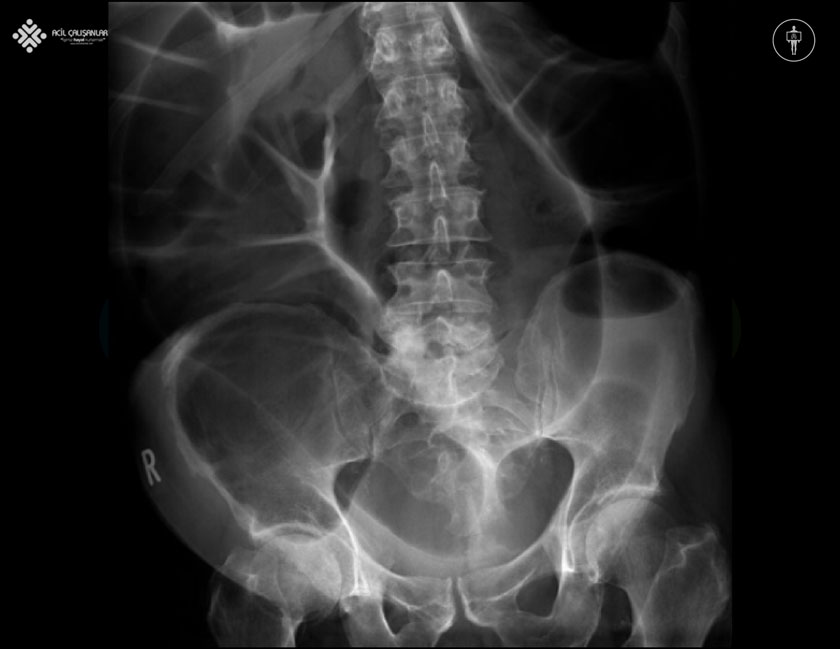

70 yaşında erkek hasta karın ağrısı şikayeti ile acil servise ayaktan başvuruyor. Hasta değerlendirildiğinde öyküsünde 3 gündür kramp tarzında ağrısının olduğu, son 5 gündür dışkılama yapmadığı belirtiliyor. Ayrıca ara ara benzer karın ağrılarının olduğu ifade ediliyor. Hasta yeşil alanda muayene ediliyor ve genel durumu iyi, vitalleri: nabız: 86 atım/dk düzenli; solunum: 18/dk; SpO2: %98; kan basıncı: 110/75 mmHg olarak ölçülüyor. Batın muayenesinde karın hafif distandü, barsak sesleri azalmış, defans ve rebound hassasiyeti yok olarak değerlendiriliyor. Muayene sonrasında acil hekimi hastadan batın grafisi ve kan tetkikleri istiyor. Hasta röntgene alanına gidip aşağıda görülen grafiyi çektiriyor ve hemen doktoruna başvuruyor. Bundan sonraki yaklaşım ne olmalıdır?

Röntgen bulguları da sigmoid volvulusu desteklemekte. Sigmoid kolonun üst kısmında genişleme ve karakteristik işaretlerin görülmesi, tanıyı güçlendiriyor. Kuş gagası", "kahve çekirdeği" belirtileri gibi spesifik bulgular, sigmoid volvulusu düşündürür. Bu durumda, hastanın tanıyı doğrulamak ve tedaviyi başlatmak için acil cerrahi konsültasyon gerekmektedir. Cerrahi müdahale, sigmoid kolonun dekompresyonu veya dönüşünün düzeltilmesi için gerekebilir. Hasta, acil cerrahi müdahale ve gerekli diğer destekleyici tedaviler için bir genel cerrahi bölümüne danışılmalıdır.